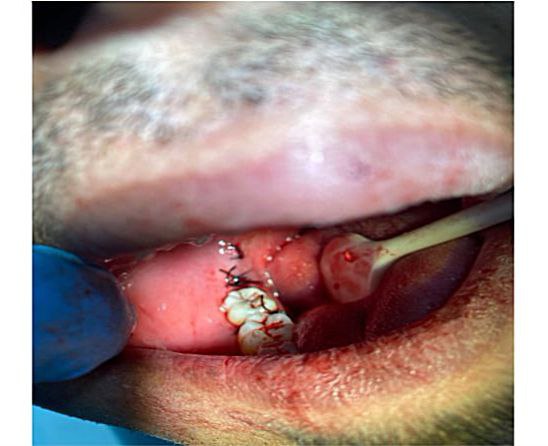

أجراء عملية قلع سن العقل لمريض في عيادة جراحة الفم

أجراء عملية قلع سن العقل لمريض يعاني من تسوس حاد وتم اجراء العملية في عيادة جراحة الفم يوم لخميس الموافق 09/11/2022<br />وتم اجراء الفحوصات الازمة في عيادة التشخيص لبفمي قبل أجراء العملية .